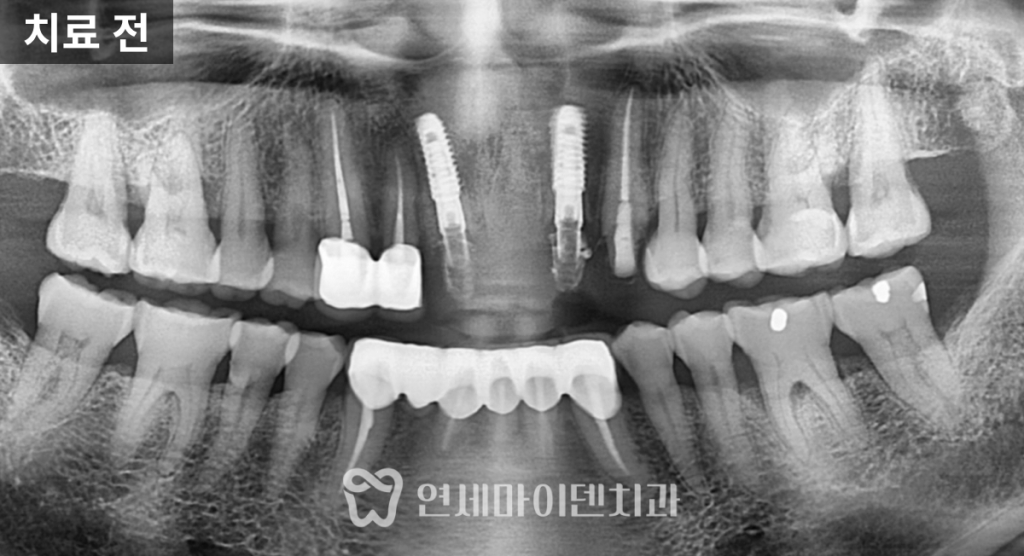

정밀 촬영 결과

두 개의 앞니 뿌리 끝, 즉 치근단 부위에서

뚜렷한 염증 소견이 확인되었습니다.한쪽 치아는

뼈 손상이 심해 예후가 불량한 상태였고,

다른 한쪽은

염증이 국소적으로 제한되어 있어

신경치료 후 경과를 지켜볼 수 있는 상황이었습니다.이에 따라 치료 계획은 다음과 같이 세웠습니다.

- 두 치아 모두 기존 보철물과 포스트를 제거

- 예후가 불량한 치아는 발치 후 즉시 임플란트 식립

- 살릴 수 있는 치아는 신경치료를 통한 보존

임플란트와 보존치료의 병행

예후가 좋지 않은 앞니는

발치를 진행한 뒤

뼈이식을 동반한 임플란트를 식립했습니다.

3D CT를 활용해

임플란트 식립 각도와 위치를

정밀하게 계획했고,

초기 고정력을 안정적으로 확보할 수 있었습니다.